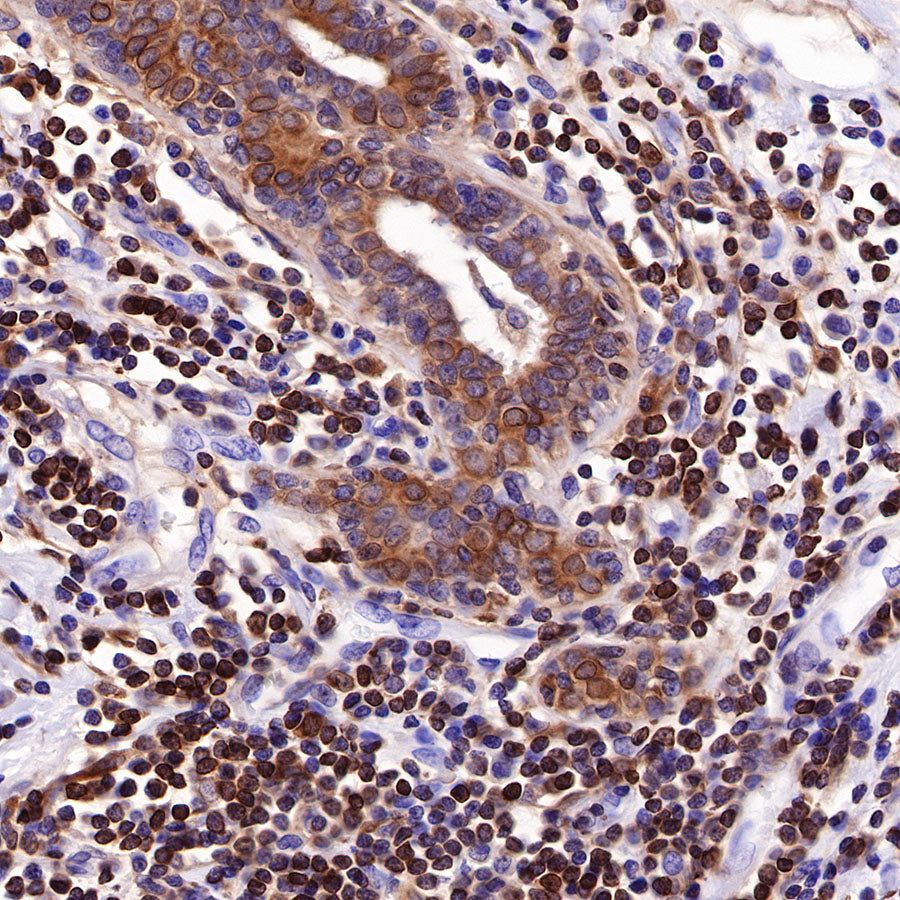

Picture

Picture

Immunohistochemistry